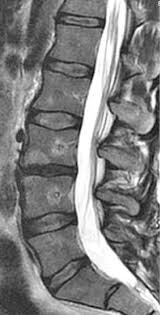

Ο σπονδυλογενής πόνος αναπτύσσεται όταν οι σπονδυλικές τελικές επιφυσιακές πλάκες υποστούν βλάβη ή φλεγμονή. Αυτό μπορεί να οδηγήσει σε χρόνιο πόνο που είναι ανθεκτικός στις συντηρητικές θεραπείες.

Η θεραπεία στοχεύει τα sinuvertebral nerves του σπονδυλικού σώματος, τα οποία μεταδίδουν σήματα πόνου από τις τελικές αποφυσιακές πλάκες. Με την απενεργοποίηση των νεύρων αυτών, διακόπτεται η ροή επώδυνων ερεθισμάτων πόνου από τον σπόνδυλο προς το κεντρικό νευρικό σύστημα. Σταδιακά ο πόνος υποχωρεί, με το τελικό αποτέλεσμα να εγκαθίσταται συνήθως μέσα σε 3 μήνες. Ο ασθενής μπορεί να επιστρέψει στην καθημερινότητά του μέσα σε μια εβδομάδα από την παρέμβαση.